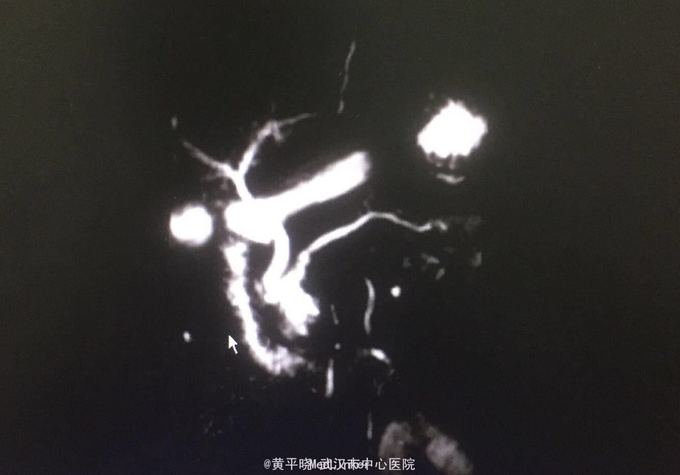

为进一步明确胰管扩张原因及排除有无胆管结石于8月27日行ERCP,术中诊断:1.IPMN(主胰管型?) 2.ERP+ENPD 十二指肠降部中段见乳头,乳头呈乳头型,开口鱼口状扩张,见胶冻样液体流出。 主胰管全程显影,胰头段主胰管及分支胰管明显扩张,主胰管直径约6mm,其内见团块状充盈缺损影,留置鼻胰管,手术经过顺利。 术后鼻胰管可见黏液胶冻样液体引流出 考虑IPMN 转胆胰外科行手术,于2015.09.03行根治性胰十二指肠切除术。 术后病理检查提示:1、(胰头钩突部)符合导管内乳头状粘液性肿瘤伴低-中级别异型增生。 2、(十二指肠)粘膜慢性炎症。 术后经抗感染、静脉及肠内营养、护肝、抑酸、抑酶、补液及维持水电解质酸碱平衡等对症支持治疗,病情恢复良好!